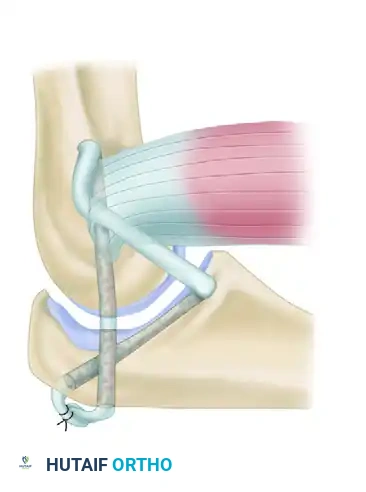

Step 3: Triceps V-Y Lengthening

Beginning proximally and using sharp dissection, reflect the aponeurosis of the triceps distally to form a flap of tissue that remains attached to the olecranon.

To perform the V-Y lengthening:

* Begin 7.5 cm proximal to the joint.

* Make an inverted "V" incision in the midline of the arm through the fibers of the triceps muscle, extending distally toward the olecranon.

* Curve this deep incision around the lateral edge of the olecranon to meet the distal end of the skin incision.